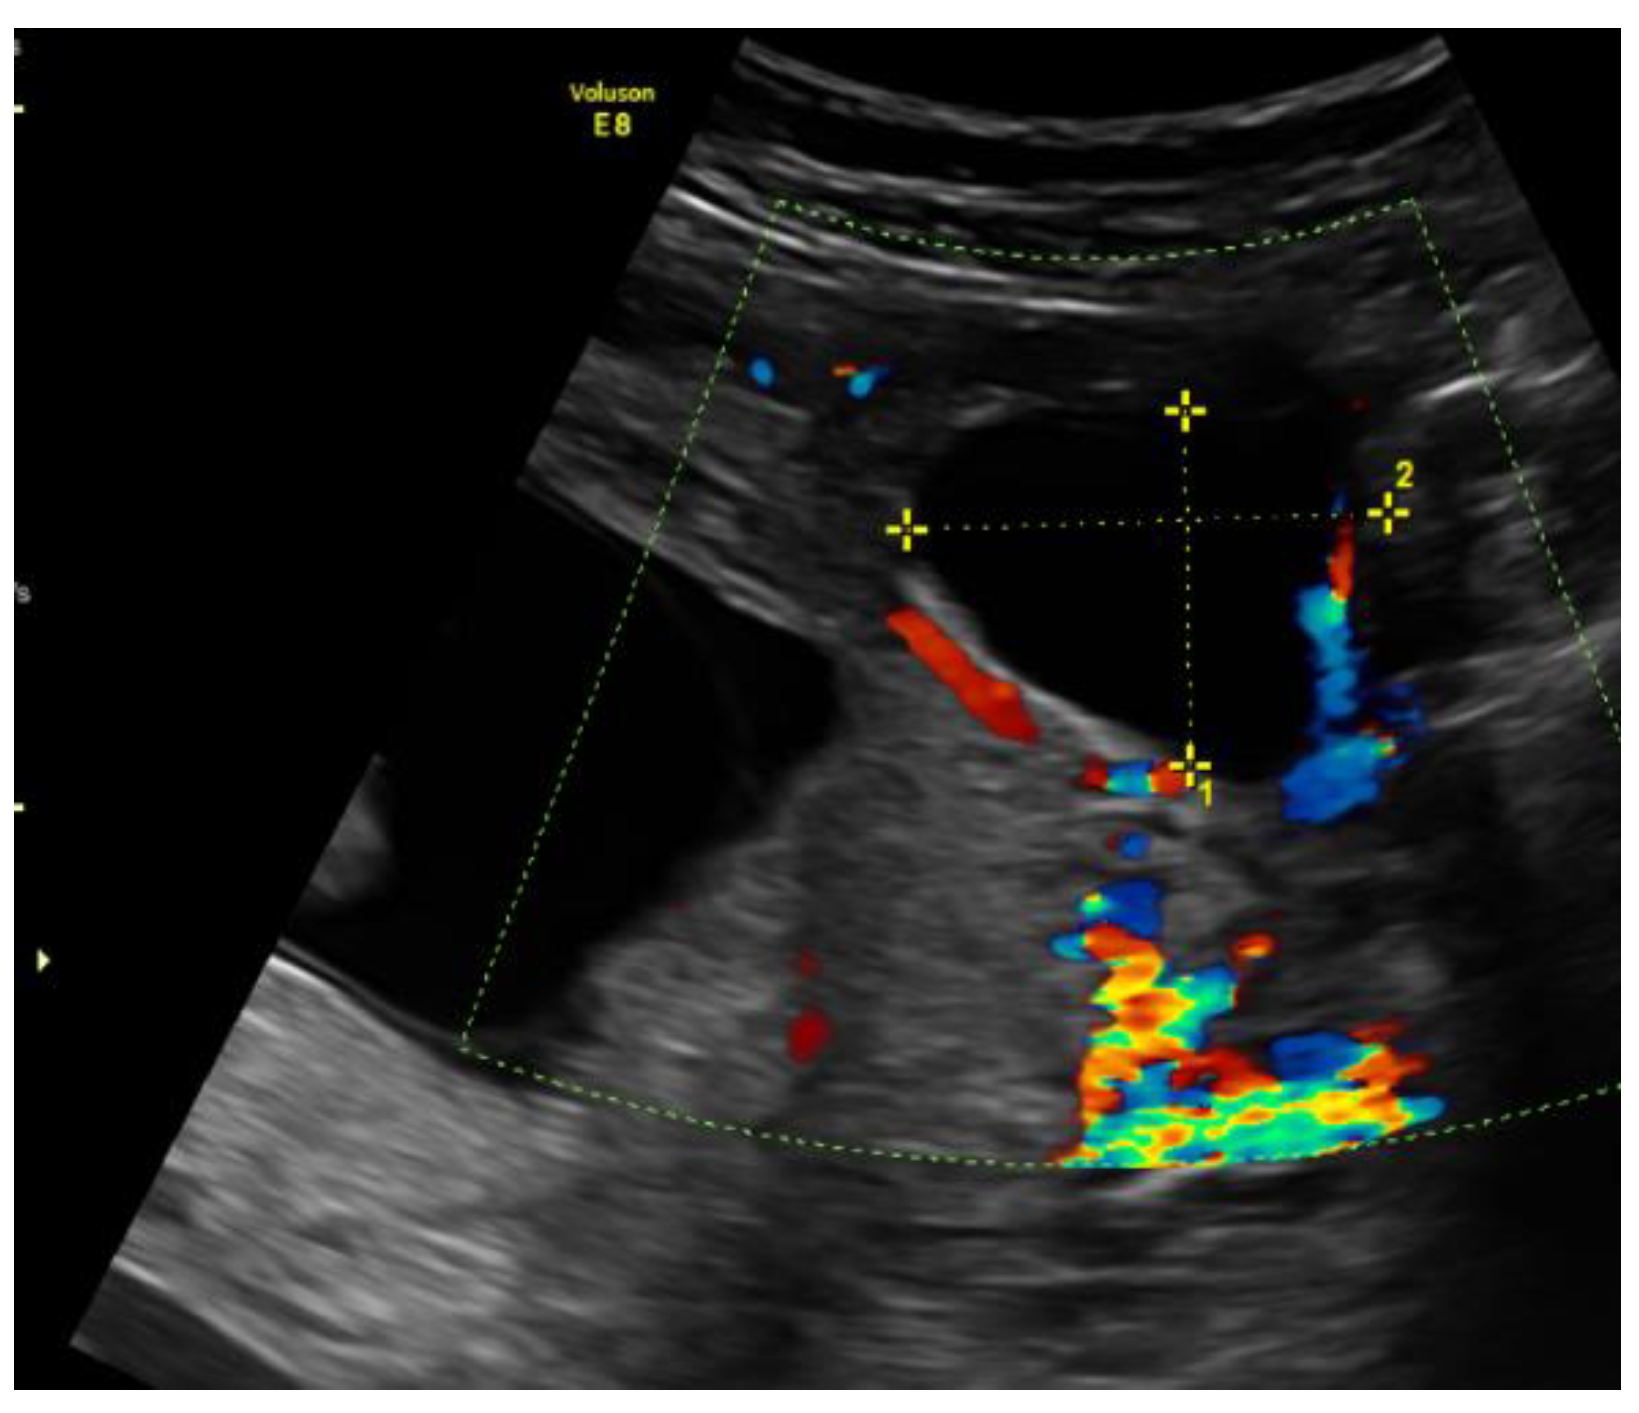

On the 22nd week of gestation, the woman was admitted to tertial level hospital complaining of pain in hypogastric and left iliac regions of the abdomen, provoked by physical exercise. Ultrasonography was performed, the remaining unchanged mass in the left cornu of the uterus was observed as well as an intraamniotic septum in the lower segment of the uterus, as shown in Figure 5 and Figure 6. The fetal growth of the intrauterine pregnancy was unaffected and matched its gestational age. Conservative treatment was chosen, the pain resolved and the patient was discharged in 2 days.

Figure 5. Left cornu of the uterus visualized by transabdominal ultrasonography at the 22nd week of gestation.

Figure 6. Left cornu of the uterus visualized by 3D transabdominal ultrasonography at the 22nd week of gestation.